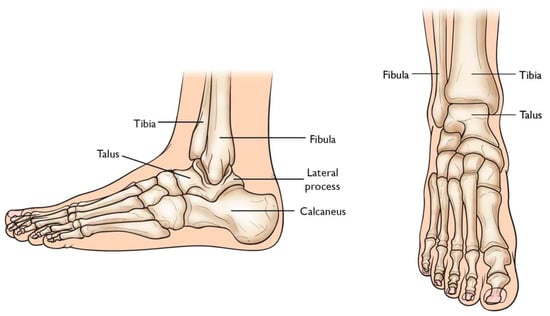

Total Ankle Arthroplasty (TAA) is an orthopedic procedure used as an increasingly popular treatment for patients with end-stage arthritis in the ankle joint. The ankle joint, also known as the tibiotalar joint, is formed from the meeting of the tibia, fibula, and talus bone [], shown and labeled in Figure 2. Wearing of the cartilage within the joint can lead to the bone ends rubbing against each other, causing bone spurs, inflammation, stiffness, osteophyte formation, and pain in the joint, overall resulting in severely decreased function [,].

Figure 2. Graphic of bones in ankle joint, including talus, fibula, tibia, calcaneus, and surrounding bones [].